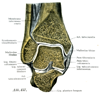

B. 自由上肢の連結

手の関節